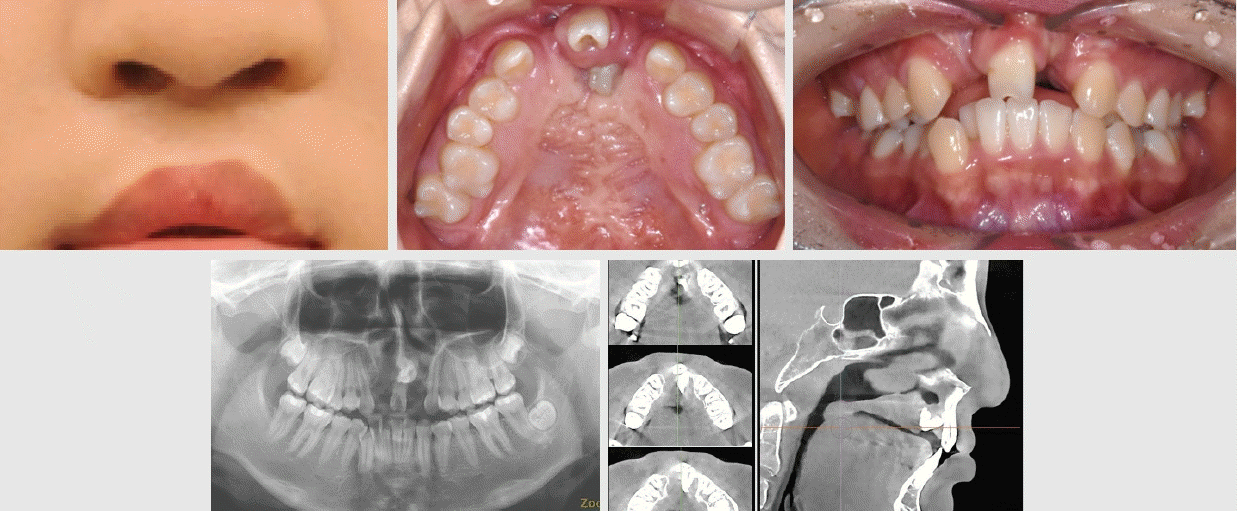

Figure 8.

Upper row: Initial intraoral frontal and maxillary occlusal views.

Lower row: Panoramic radiograph, axial and sagittal views